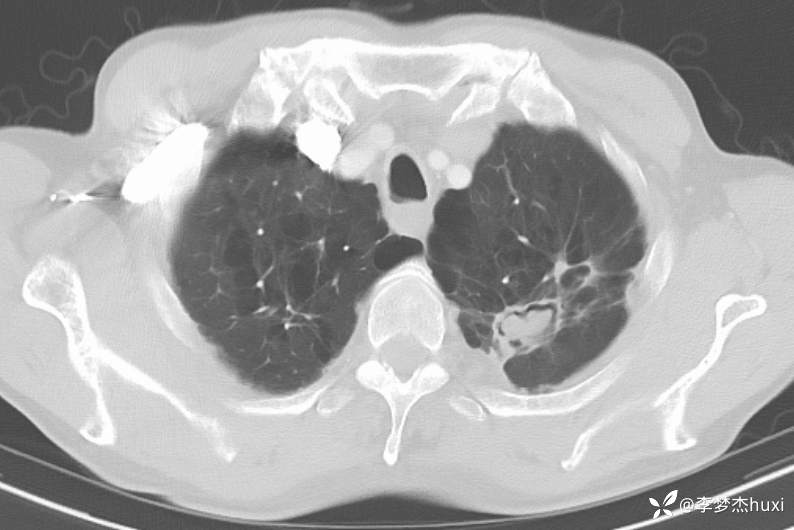

1.现病史:患者老年 男,患者于入院前7天“感冒”后出现咳嗽、咳痰,为白痰,不易咳出,伴胸闷憋气,活动后加重,病初发热,最高达38.0℃,无胸痛,无咯血,无腹痛、腹泻,无恶心、呕吐,无尿频、尿急、尿痛,院外给予口服药物(自诉口服药物,具体药物名称不详)治疗,病情无明显好转,6-13于我院门诊查胸部CT:左肺上叶软组织密度影-性质待定,双肺炎症,双肺气肿,双肺大泡,双肺部分实性结节-炎症?双肺实性结节,主动脉及冠状动脉钙化,双侧胸膜局限性增厚;肝脏多发囊性病变。6-14查胸部增强CT:左肺上叶空洞-真菌感染?占位不除外;双肺炎症,双肺气肿,双肺大泡,双肺部分实性结节-考虑炎症,双肺实性结节,主动脉及冠状动脉钙化,双侧胸膜局限性增厚;肝脏多发囊性病变;今日为进一步诊治来我院;门诊以“肺空洞”收入院。